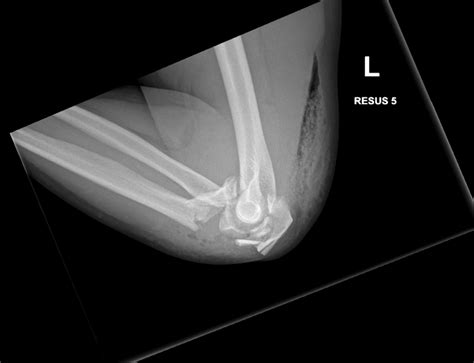

• X-Rays: X-rays are the primary imaging tool used to diagnose hairline fractures. They can show the crack in the bone and help determine the extent of the injury.

• CT Scans: In some cases, a CT scan may be ordered to provide a more detailed view of the bone and surrounding tissues.

• MRI Scans: An MRI may be used to assess soft tissue damage and confirm the diagnosis of a hairline fracture.